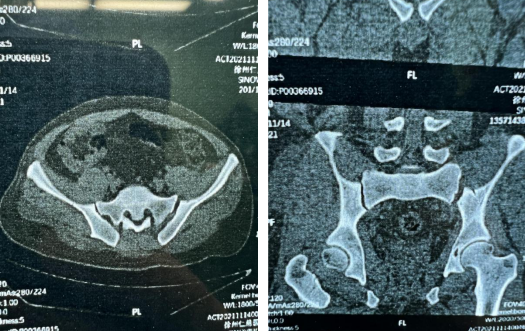

11月中旬,创伤骨科就收治了一位因车祸导致骨盆骨折的患者,经检查后发现为骨盆多发性骨折,左骶髂关节半脱位,耻骨上下支也有骨折。

创伤骨科任海东主任和手术团队经过术前讨论,决定借助新引进的骨盆牵引床、骨盆微创复位系统为患者进行“骨盆骨折微创复位内固定术”。

一般的手术床不具备牵引复位的功能,而betway在线登陆新引进的骨盆牵引床可以让患者很容易地在C臂机透视下,通过调整牵引装置达到良好的复位,在电脑上规划螺钉方向,并且在术中操作时始终保持良好的复位效果,不易发生体位改变,保障手术安全进行。